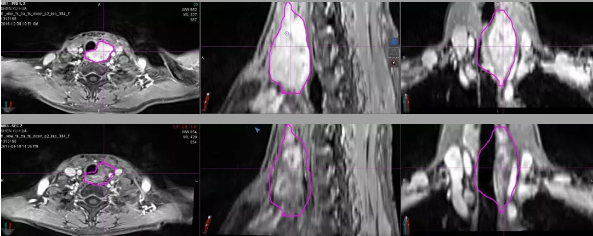

【上图】重离子放疗前

【下图】重离子放疗后3个月

病例A:颈部腺样囊性癌,放疗后3个月肿块明显退缩,疗效评价为部分缓解。